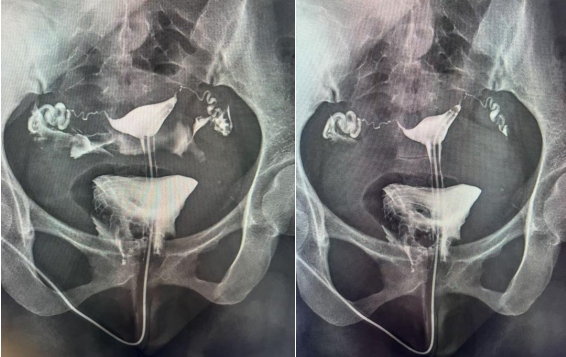

子宮輸卵管造影是通過導(dǎo)管經(jīng)陰道、子宮頸向?qū)m腔及輸卵管內(nèi)注入造影劑,利用X線診斷儀透視并拍片,根據(jù)造影劑在子宮、輸卵管及盆腔內(nèi)的顯影情況,來了解和判斷子宮腔形態(tài),是否畸形、粘連,輸卵管是否通暢,以及輸卵管阻塞的部位。常用于不孕癥、輸卵管再通、子宮畸形等疾病的診治。如